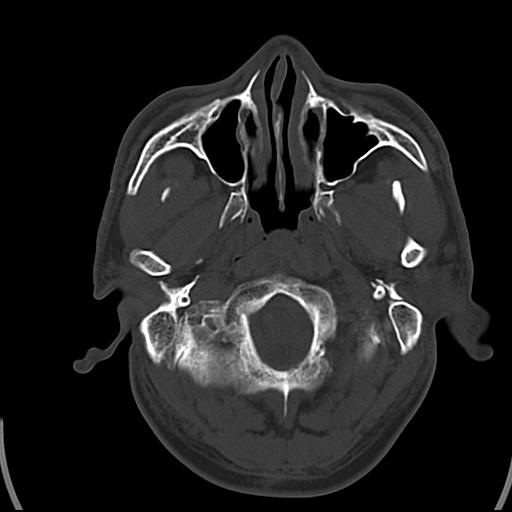

头皮下高密度结节影???临床上在老年男性比较常见。大家看看是什么?成因是? 本例患者,男性,51岁。外伤来诊。无染发史及发根植入史。

考虑异物。

皮下钙化点

没见过,可能为毛囊钙化。